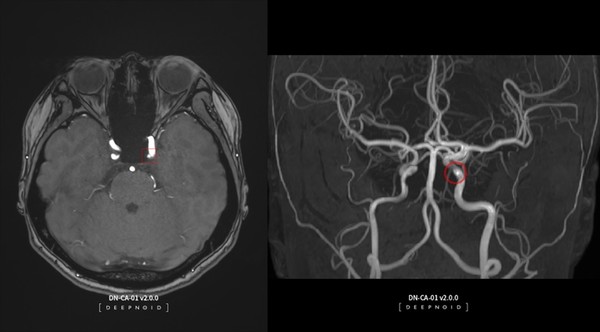

딥노이드가 ‘딥뉴로’의 의료기관 도입 본격화를 통해 국내외 시장에서의 입지 확장에 나선다고 밝혔다. 딥뉴로는 뇌 MRA 영상을 활용한 AI 기반의 뇌동맥류 검출 진단보조 솔루션으로, 8월 혁신의료기술로 지정된 바 있다.

혁신의료기술에 대한 보건복지부의 고시 발령에 따라 11월부터 의료현장에서 환자에게 딥뉴로의 직접 활용이 가능하게 됐으며, 이에 따른 도입 본격화가 기대된다는 설명이다.